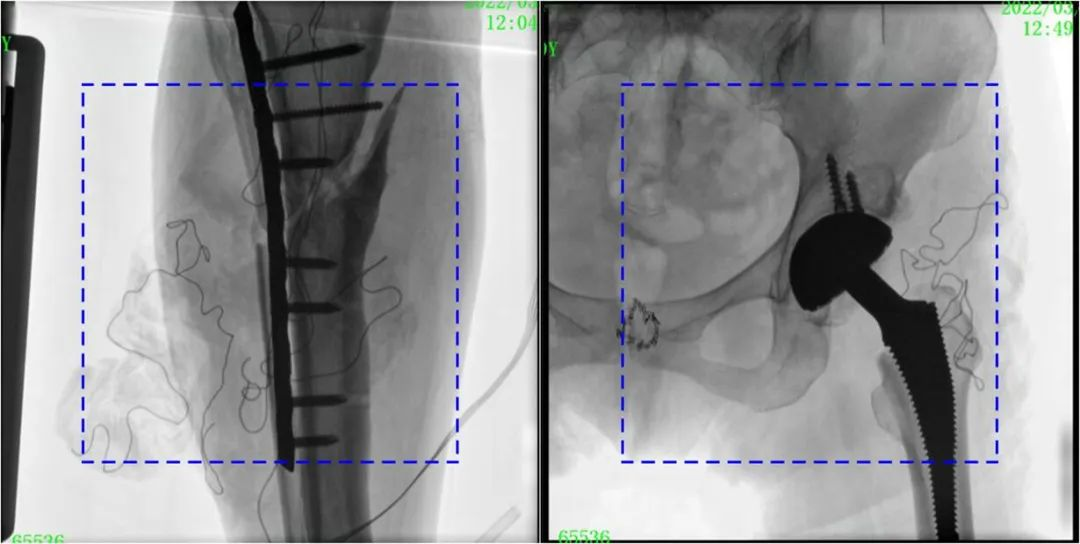

與傳統(tǒng)的21CM×21CM成像尺寸相比,普愛醫(yī)療大平板一體式C形臂具有30CM×30CM更大成像尺寸,能夠一次成像5.5節(jié)椎體,呈現更全面的影像信息,即便是手術經驗不豐富的年輕醫(yī)生也能通過圖像迅速判斷椎體節(jié)段、定位手術部位,避免因為視野不足而造成的多次定位、反復曝光,提高效率的同時避免過量攝入輻射。

普愛醫(yī)療大平板一體式C形臂圖像與傳統(tǒng)圖像對比(藍色虛線內為傳統(tǒng)21CM×21CM平板的成像區(qū)域)